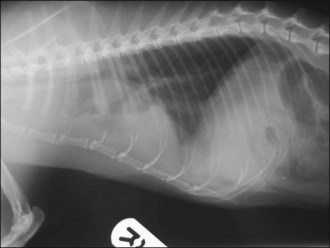

In the author’s experience, neoplasia and congestive heart failure (see Ch. 31) are the two most common causes identified in cats (see Figures 32.1-32.4).

image image image image

Figure 32.4 Right lateral and dorsoventral thoracic radiographs of a cat with idiopathic chylothorax (a, b) before and (c, d) after thoracocentesis. The post-drainage films were taken the day after under general anaesthesia; an oesophageal stethoscope is visible.